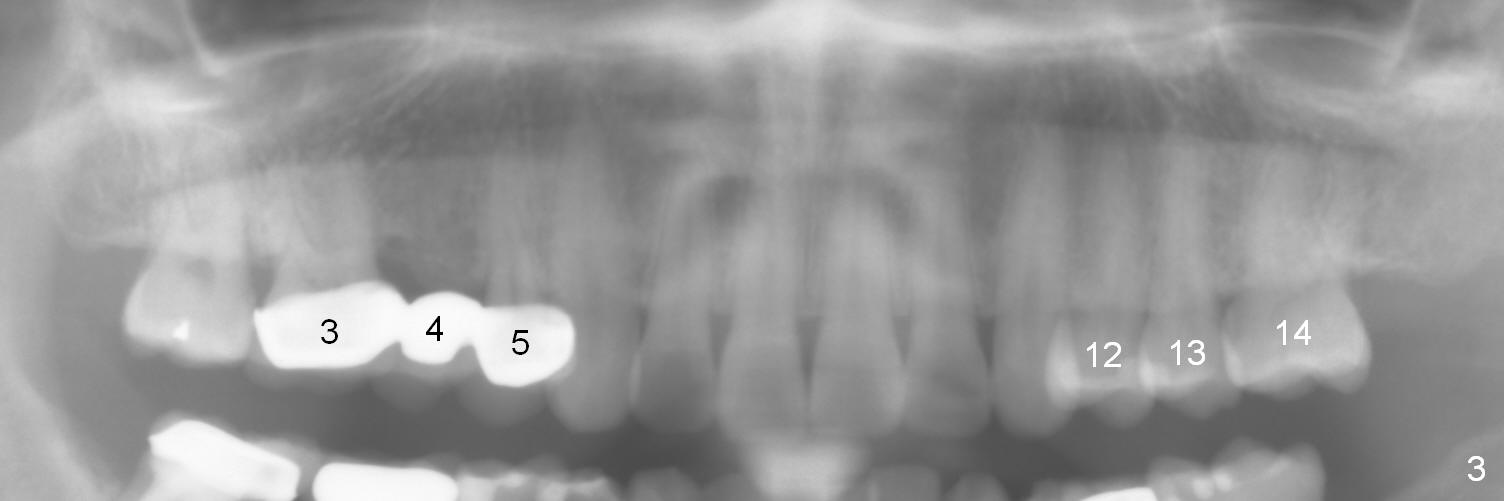

Ms. Li, a 34-year-old lady, had the upper right fixed partial denture made by an unlicensed dentist in California 10 years ago (Fig.1: #3-5). The gingival margin palatal to the retainers is erythematous (Fig.1 arrows). The patient's chief complaint is gum bleeding. The retainer at #3 is over-contoured buccopalatally (Fig.1, as compared to #14 in Fig.2), while the one at #5 is over-contoured buccopalatally and mesiodistally (compare to #12 in Fig.2). Panoramic X-ray (Fig.3), bitewing (Fig.4) and periapical film (Fig.5) all confirm that the bridge is over-contoured and that the retainers #3 and 5 have open margin (Fig.4 arrowheads). To improve oral hygiene and save the abutment teeth #3 and 5, it is in the patient's best interest to remove the bridge, place an implant at #4 and fabricate single-unit crowns at #3 and 5. Three to four months later, pyogenic granuloma develops between #4 and 5 (Fig.6 *) with generalized gingival erythema apically. The pontic at #4 and the retainer at #5 are to be removed first. An implant will be placed at #4 (Fig.7) with conjoined provisional at #4 and 5. The initial depth of osteotomy is 13 mm with Sinus Master Kit.